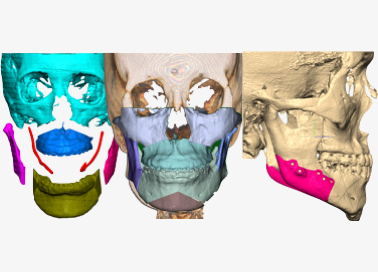

Jaw segmentation

- Skull data can be freely osteotomized according to technique preferred by oral surgeon

- Osteotomy position, range, & amount can all be adjusted depending on patient characteristics

- Combining osteotomy segments verifies anatomical changes during bone deletion & bone movement for feasible & precise surgical plan

Facial Reconstruction Surgery

Customized facial reconstruction solutions